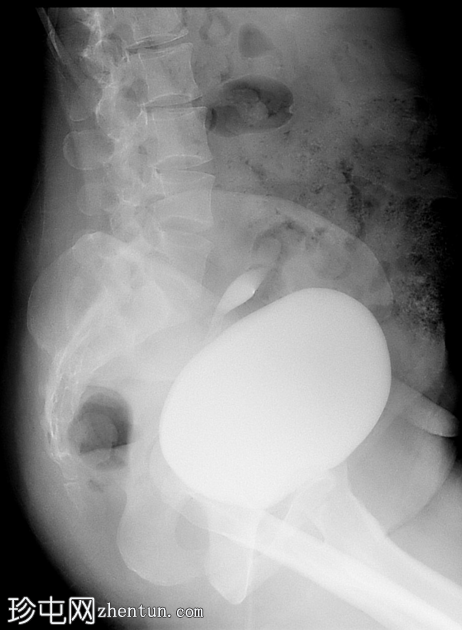

侧位

经Foley导尿管向膀胱内注入约700毫升造影剂。

子宫内可见造影剂积聚,膀胱上表面与子宫之间存在异常瘘管连接。同时可见造影剂从输卵管溢入腹腔。

影像

学表现符合膀胱子宫瘘。